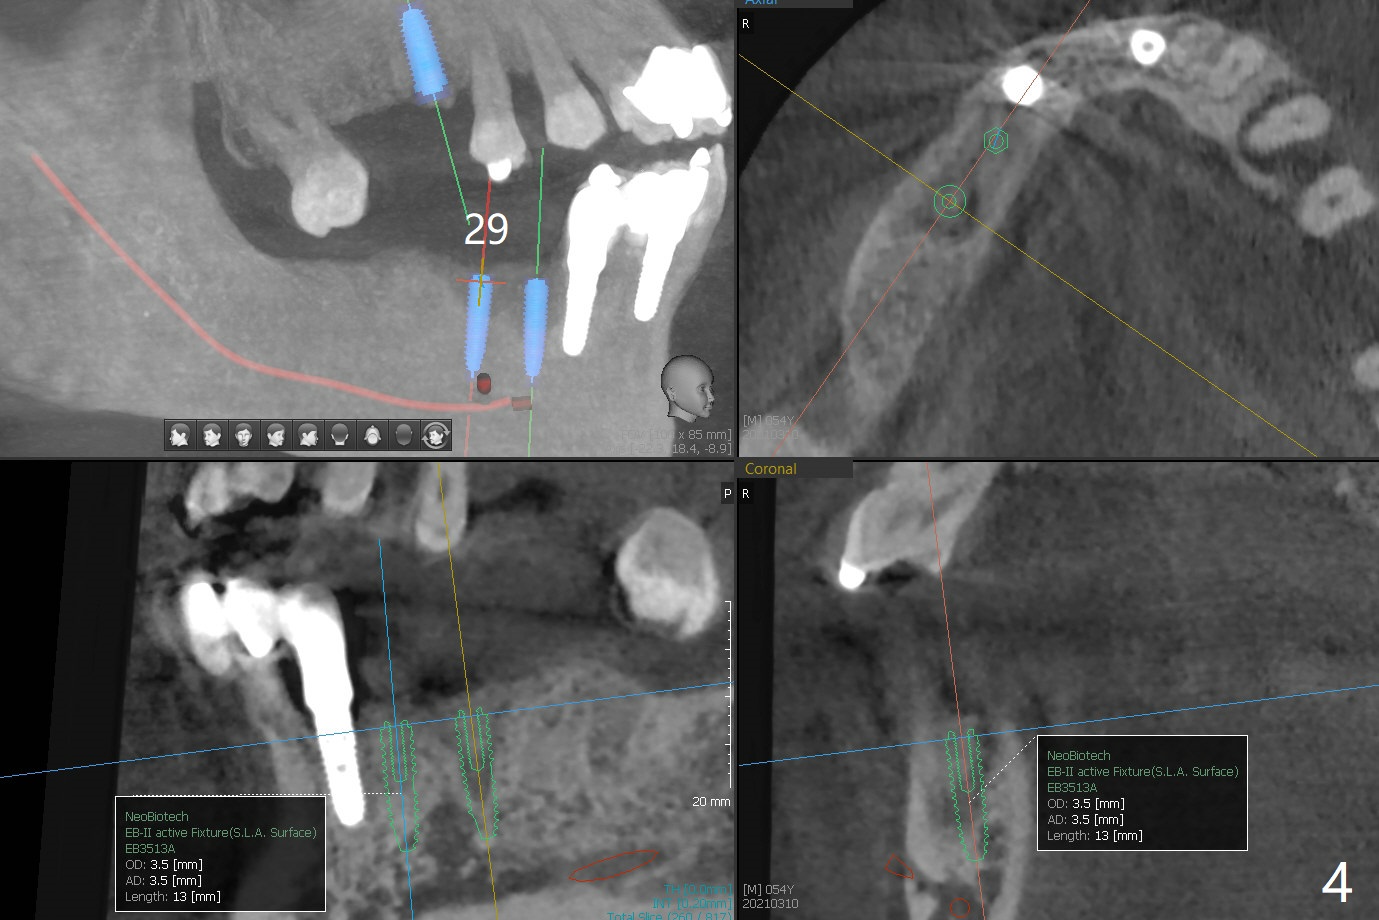

54岁男,28,29植骨后5个月,回来要求3,13,28,29种植(图一)。3号牙需要切开除去残根(图二:*),然后导板种植,准备两个PRF膜。为了保证植牙间距离,尝试在28,29处植入3.5x13毫米植体(图三,四)。在13号牙种植时(图五),考虑12号牙腭侧植骨(图六)。为了减少对12号牙咬合创伤,考虑4个植牙即刻修复。